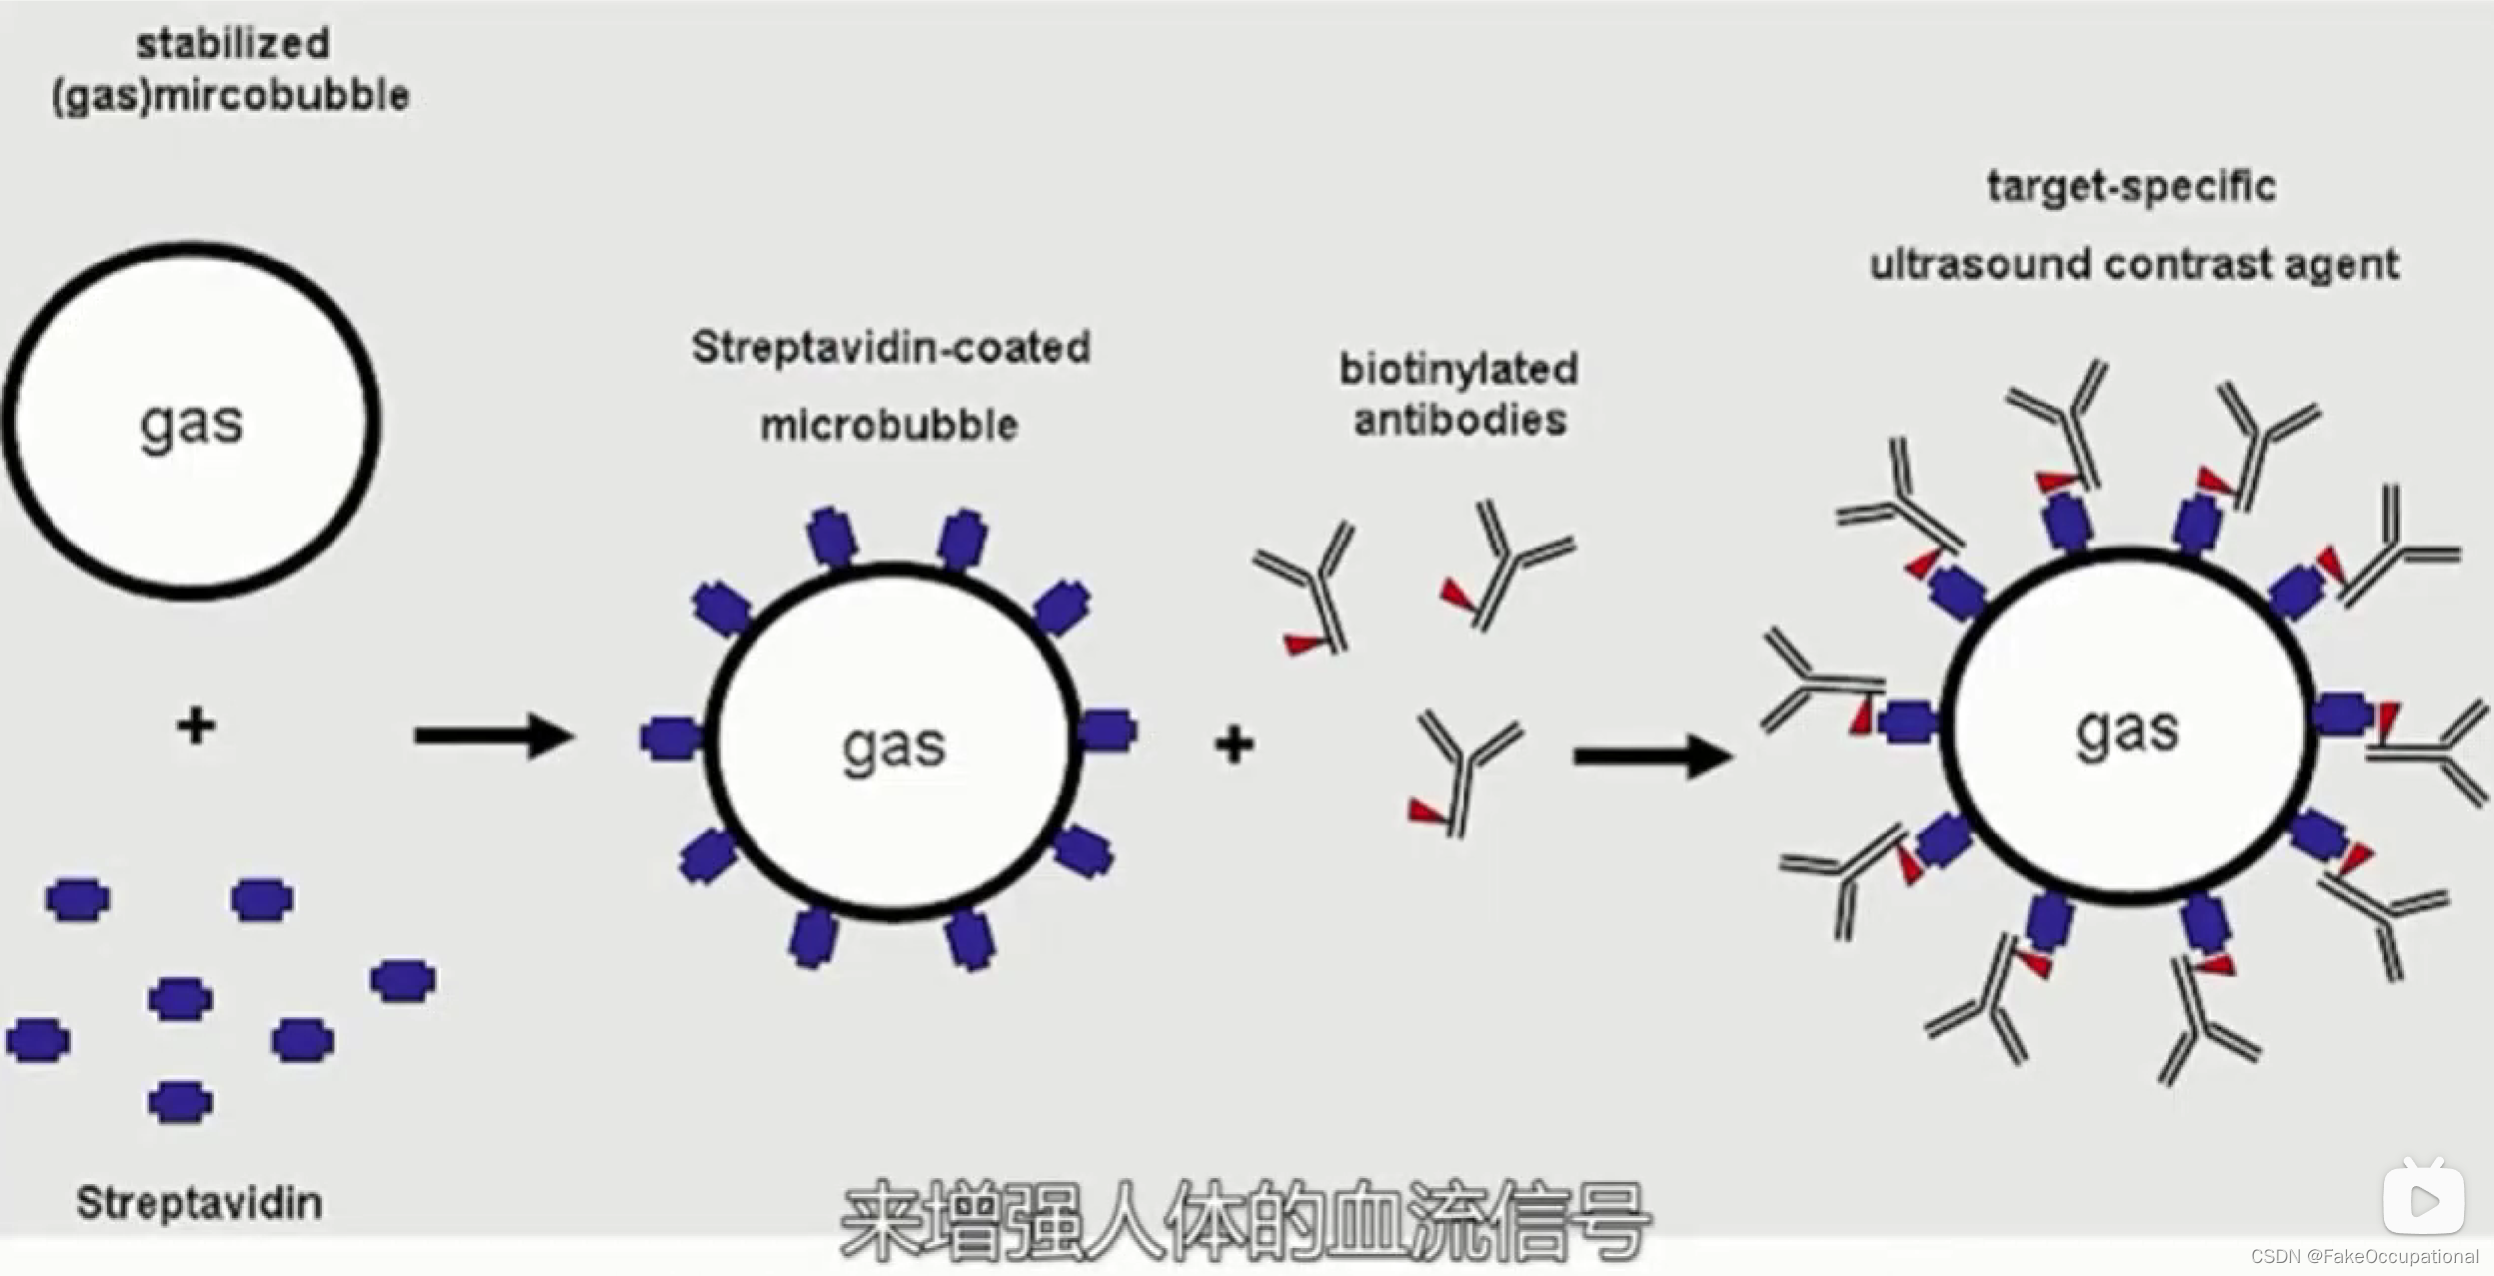

2.超声造影

乳腺超声进展